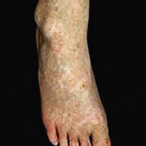

Fig. 36.17

Reticulate acropigmentation of Kitamura.

Courtesy Department of Dermatology, Keio University, School of Medicine, Tokyo, Japan.